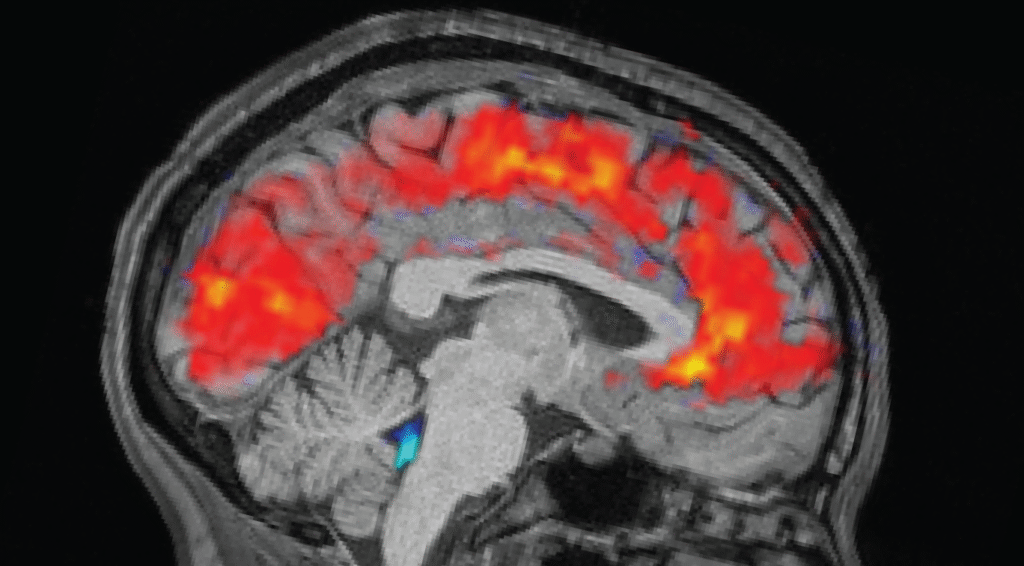

The rested people slept between 6.5 and 9 hours at home, while the sleep-deprived people stayed up all night in the lab. The morning before each experiment, the team fitted participants with electroencephalogram (EEG) caps and recorded their brain waves with electrodes. At the same time, participants underwent functional MRI (fMRI) scans to reveal patterns of blood and CSF flow in the brain. An eye tracker measured the participants’ pupil size.

As expected, participants took longer to notice the stimuli when they were tired and missed cues more often than when they were well-rested. However, the researchers were surprised to see huge CSF pulsations and slow brain wave patterns in the exhausted people. Both are normally observed during non-REM sleep.

Specifically, this pattern was similar to that seen as humans transition from stage N1 to stage N2, the first two of the three stages of non-REM sleep that people experience during each sleep period. “This has previously only been seen at this scale during sleep,” Lewis said.